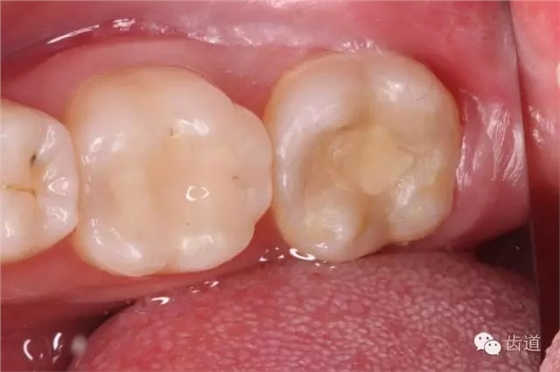

一診(2015.01.25): 主訴:左下后牙咬食疼痛約2天 既往史:無(wú)特殊 3年前因左下后牙蟲(chóng)牙不適,已在外院治療,治療后癥狀消失,約2天前,左下后牙開(kāi)始出現(xiàn)咬合時(shí)劇烈疼痛,無(wú)冷熱刺激痛,無(wú)夜間痛,否認(rèn)咀嚼硬物史,約1天前,開(kāi)始出現(xiàn)自發(fā)性跳痛,咬合可適當(dāng)緩解疼痛,未自行服用藥物,未在外院治療,癥狀持續(xù)為緩解,遂于我院就診。 口外檢查:面部對(duì)稱,無(wú)腫脹 口內(nèi)檢查: 36合面樹(shù)脂樣材料充填,邊緣密合,牙體及修復(fù)材料表面均未見(jiàn)明顯缺損及裂紋,未探及繼發(fā)齲,探痛-,叩痛-,松動(dòng)-,冷水刺激痛-,未探及牙周袋及附著喪失,牙齦無(wú)紅腫,電活力測(cè)試平均值為15;37合面樹(shù)脂樣材料充填,邊緣密合,牙體及修復(fù)材料表面均未見(jiàn)明顯裂紋,未探及繼發(fā)齲,探痛-,叩痛+++,松動(dòng)-,冷水刺激痛-,未探及牙周袋及附著喪失,牙齦無(wú)紅腫,電活力測(cè)試無(wú)反應(yīng);38埋伏阻生,可探及齦下牙冠,探痛-,牙齦無(wú)紅腫。 26、27牙體未見(jiàn)明顯充填物、缺損、齲壞及裂紋,探痛-,叩痛-,松動(dòng)-,冷水刺激痛-,未探及牙周袋及附著喪失,牙齦無(wú)紅腫; 影像學(xué)檢查: 全景片及X線根尖片顯示36合面充填物影像,靠近髓腔,未見(jiàn)根折影像,未見(jiàn)牙槽骨吸收,未見(jiàn)根分叉透射影,未見(jiàn)根尖周暗影;37合面充填物影像,靠近髓腔,未見(jiàn)根折影像,未見(jiàn)牙槽骨吸收,未見(jiàn)根分叉透射影,根管影像清晰,根中上三分之二粗大,根尖三分一分為近遠(yuǎn)中兩根管,形態(tài)均呈弧形,根尖周膜連續(xù)性中斷,根尖周透射影明顯,進(jìn)一步測(cè)量顯示:髓室頂最低點(diǎn)到髓底的距離a,與髓室頂最低點(diǎn)到根尖孔的距離b,兩者關(guān)系為a/b>0.2;38近中阻生,牙根尚未發(fā)育完全,未見(jiàn)冠周明顯透射影像;。CBCT片顯示:在水平斷層上,可見(jiàn)37根管在根尖三分之一為彎曲偏向頰側(cè)的C型,存在近遠(yuǎn)中兩個(gè)主根管,中間峽部相連;在矢狀斷層上,可見(jiàn)37根管遠(yuǎn)中根尖孔擴(kuò)大,遠(yuǎn)中根尖狹窄處位于離解剖根尖約1mm處 37慢性根尖周炎急性發(fā)作(牛牙癥) 37擬行根管治療+嵌體間接修復(fù)或根管治療+直接樹(shù)脂充填,告知患者嵌體間接修復(fù)及樹(shù)脂直接充填兩種方法的優(yōu)缺點(diǎn)、診療過(guò)程及費(fèi)用,患者知情,同意選擇根管治療+嵌體間接修復(fù)方案,簽署術(shù)前知情同意書。 37無(wú)局部麻醉下,橡皮障放置,涂布邊緣封閉劑,顯微鏡下,合面開(kāi)髓,死髓,無(wú)惡臭,無(wú)滲出液,Endo-Z開(kāi)髓鉆揭全髓頂,探及髓腔內(nèi)壞死牙髓組織,3%次氯酸鈉浸泡髓腔5min,超聲清理髓腔,顯微鏡下探及近遠(yuǎn)中主根管,及根管間峽部。通過(guò)放入初尖銼及電子根管根管長(zhǎng)度測(cè)量?jī)x確定根管長(zhǎng)度為18mm,利用手用K銼將根管預(yù)備至15#,再利用Waveone 25#預(yù)備根管至工作長(zhǎng)度,之后,10ml 3%次氯酸鈉沖洗根管,超聲無(wú)菌水蕩洗,選取25#06錐度牙膠為主牙膠,拍攝示尖片,顯示到達(dá)根管長(zhǎng)度。然后,17% EDTA凝膠處理根管壁,5ml 2%氯己定溶液完成終末沖洗,螺旋輸送器導(dǎo)入氫氧化鈣,放置棉球1,ZOE暫封。

4. 初步開(kāi)髓

5. Endo-Z揭全髓室頂

6. 可見(jiàn)髓腔內(nèi)壞死牙髓組織,無(wú)滲出